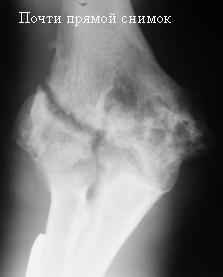

Стойкая комбинированная контрактура правого локтевого сустава

Увжаемые коллеги! На консультации больной со стойкой комбинированной контрактурой правого локтевого сустава.

В прошлом - спортсмен, сейчас охранник. Травма 2 августа 2008г., автодорожная. Оперирован в одной из больниц города. Остеосинтез, два месяца гипс. Объем движений с тех пор не изменился. Боли после физнагрузки (пытается тренироваться).

Имеется ложный сустав мыщелка плечевой кости.